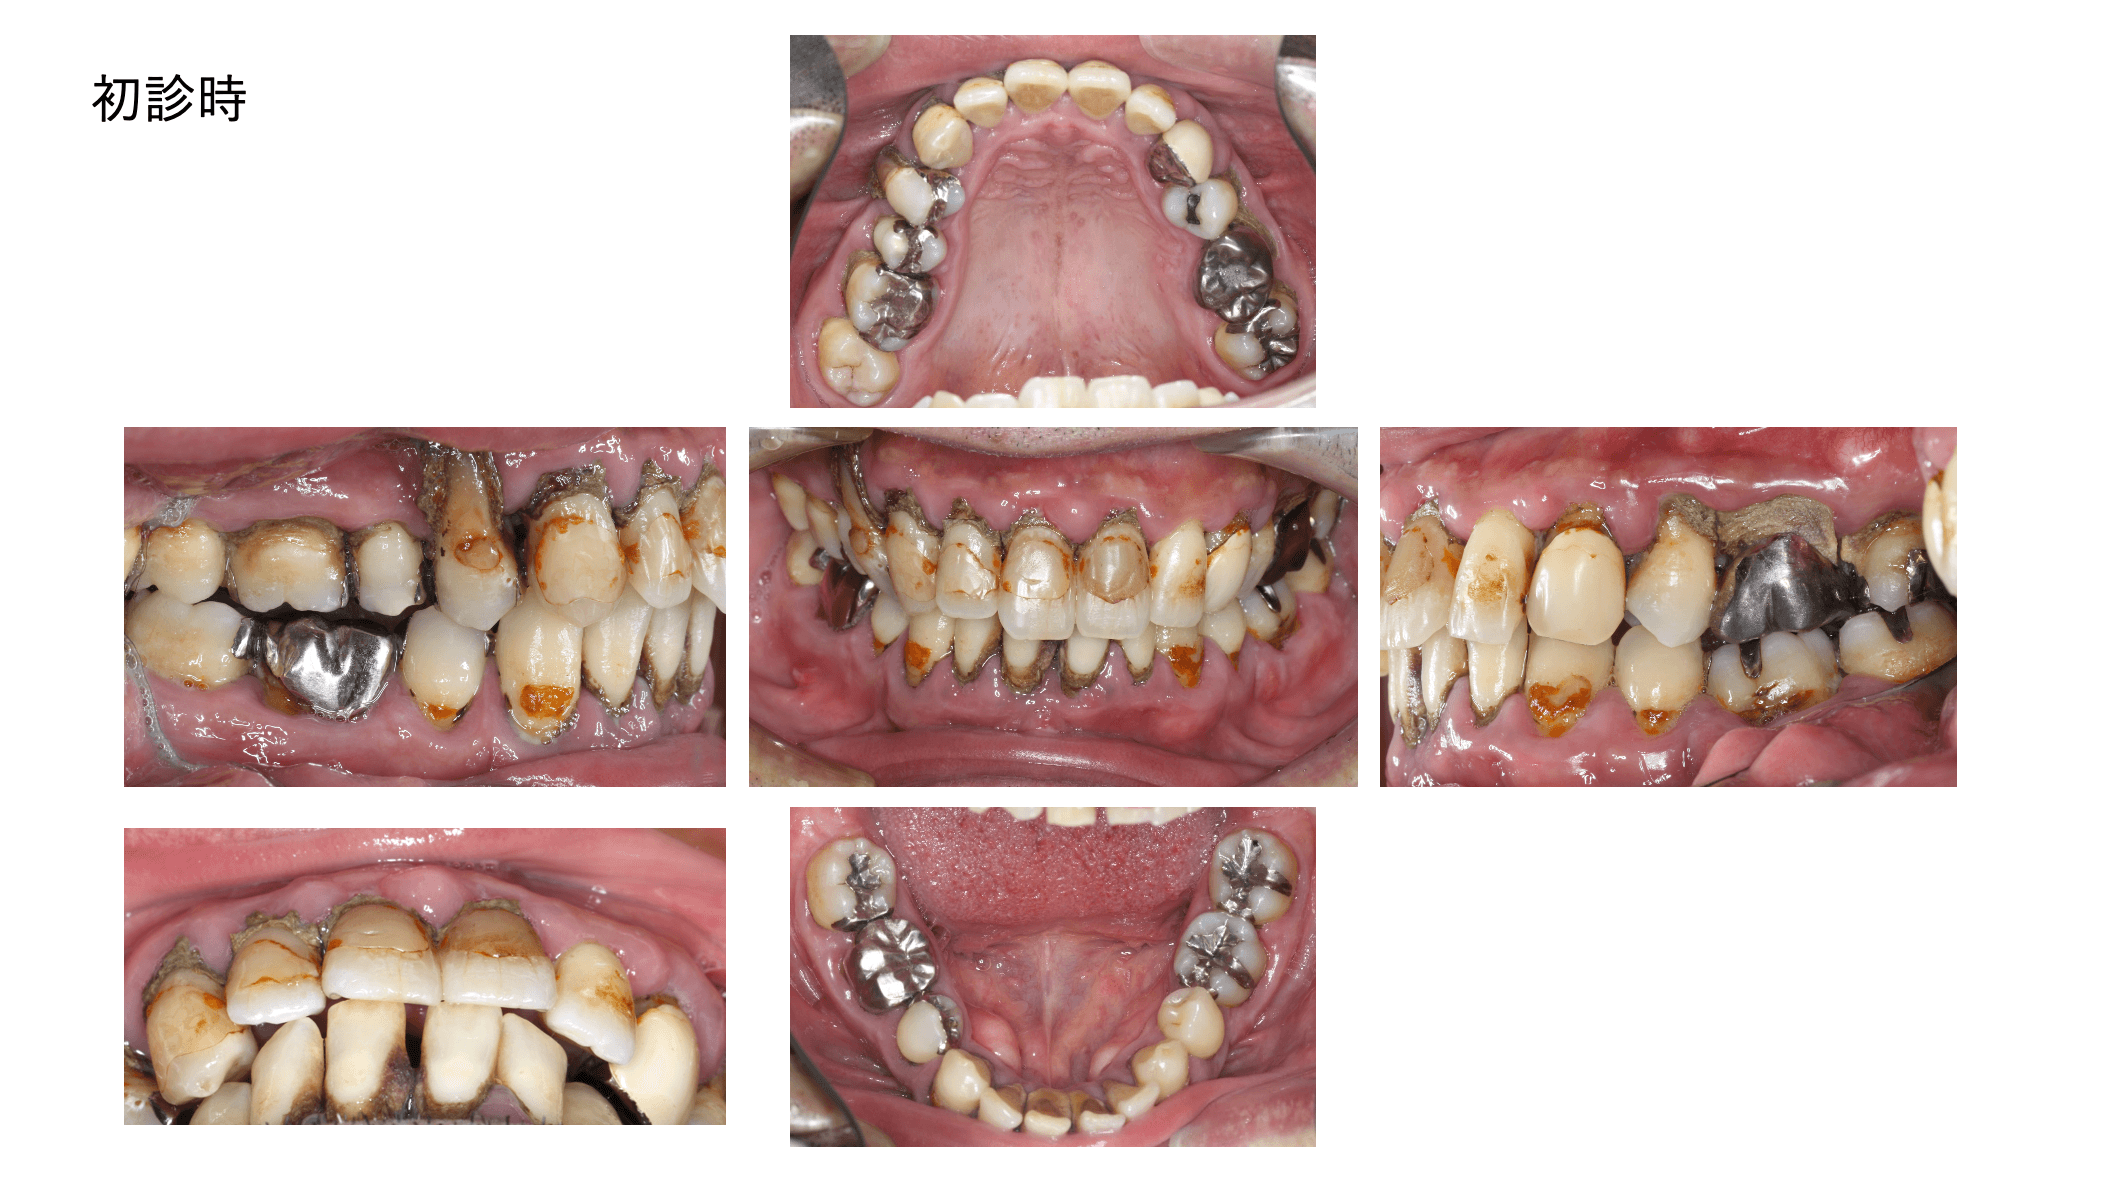

歯周ポケット測定不能。教科書的に100%抜歯の重度慢性歯周炎。原因除去療法とマイクロスコープを使った低侵襲の歯周組織再生療法により、抜歯を回避して回復した症例です。

指数病の治療をしたいということでご来院された40代の男性です。写真で分かるとおり歯石がびっしりと着いており歯周炎により歯茎の腫れも相当ある状態でした。

- 広汎型慢性歯周炎 ステージ3 グレードC

と診断をいたしました。